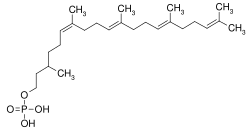

| The formation of the LLO is initiated by the synthesis of the polyisoprenyl dolichol from farnesyl, a precursor of cholesterol biosynthesis. This step involves at least three genes, DHDDS (encoding dehydrodolichyl diphosphate synthase that is a cis-prenyl transferase), DOLPP1 (a pyrophosphatase) and SRD5A3, encoding a reductase that completes the formation of dolichol. | Recently, exome sequencing showed that mutations in DHDDS cause a disorder with a retinal phenotype (retinitis pigmentosa, a common finding in CDG patients.[11] Further, the intermediary reductase in this process (encoded by SRD5A3), is deficient in SRD5A3-CDG (CDG-Iq).[12] | |

| Dol is then activated to Dol-P via the action of Dol kinase in the ER membrane. | This process is defective in DOLK-CDG (CDG-Im).[13] |  |